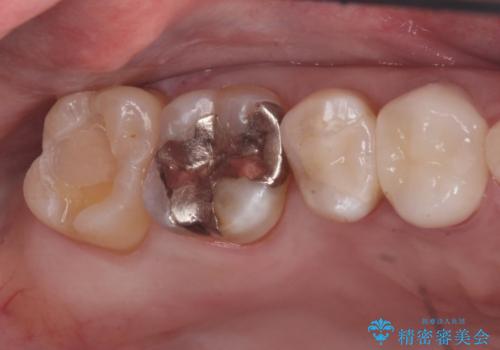

奥の歯に穴が空いている

- 奥の歯に穴が空いているとの事で来院。

拡大鏡下で虫歯を全て除去しゴールドインレーにて治療しました。